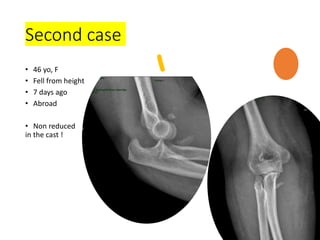

Second case

• 46 yo, F

• Fell from height

• 7 days ago

• Abroad

• Non reduced

in the cast !

What to do ?